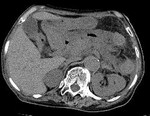

[画像診断]壊死性膵炎のCT所見、読影における注意点について(特に内部ガス) 2011-07-06